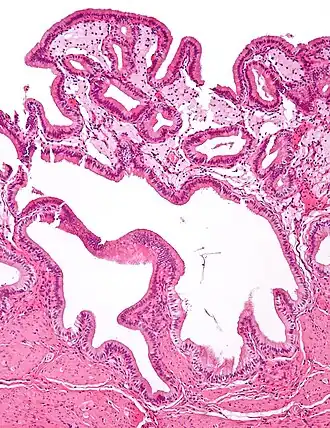

Micrograph of cholesterolosis of the gallbladder

Micrograph of cholesterolosis of the gallbladder -